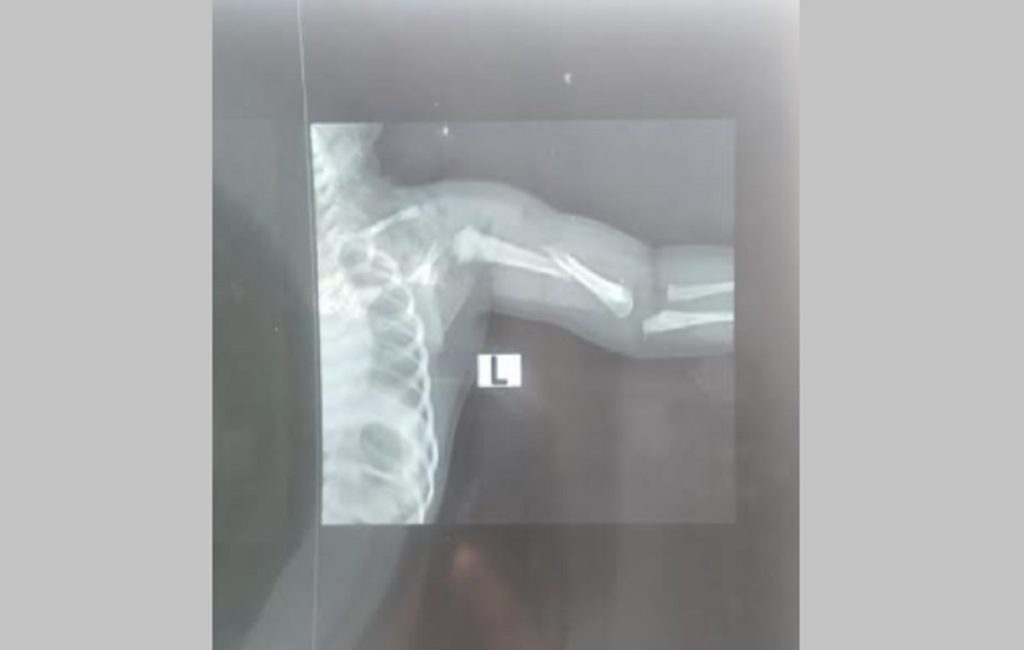

তখন এর কারণ জিজ্ঞাস করলে তারা বলেন, শিশুটির জন্মগত সমস্যা হয়েছে, তাকে হাসপাতালের চেয়ারম্যান ডা. আবু হামেদ বাবু দেখে বলতে পারবেন। এরপর ৮ মার্চ শিশুটির কান্না না থামলে ডা. আবু হামেদ বাবু তাকে দেখে জানান, শিশুটির জন্মের সময় হাত পিছনে ছিল তাই দুর্বলতা থেকে এমন হচ্ছে। তারপর তিনি এক্সরে করে জানান শিশুটির হাত ভাঙা। এই ঘটনায় হাসপাতালের পক্ষ থেকে কোনো ব্যবস্থা না নেয়ায় শিশুটির মামা মোস্তাকুল ইসলাম রোববার জেলা সিভিল সার্জন কার্যালয়ে লিখিত অভিযোগ দিয়েছেন।

ওই শিশুর নানি পারভীন বেগম জানান, নিয়মিত যে চিকিৎসকের তত্ত্বাবধানে ছিলাম তিনি আমাদের নবজাতকের সবকিছু নরমাল ছিল বলেন। কিন্তু সিজারের পর তারা শিশুটিকে আমাদের কাছে হাত ভাঙা অবস্থায় দেন।

অভিযোগকারী মোস্তাকুল ইসলাম বলেন, পেটের ভেতরে শিশুটির হাত পেছনে থাকায় সেটি ভেঙে গেছে বলেছেন ওই হাসপাতালের চিকিৎসক-নার্সরা। ওই সময় হাত ভেঙে গেলে শিশুটি জীবিত জন্ম নিতো না।